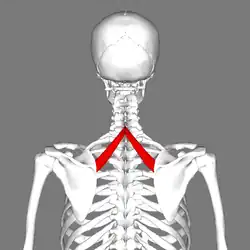

Le muscle petit rhomboïde est un muscle pair du dos reliant l'épaule au rachis.

Le muscle petit rhomboïde forme la partie supérieure du muscle rhomboïde et est situé sous le muscle trapèze.

Le muscle petit rhomboïde nait des processus épineux de la septième vertèbre cervicale et de la première vertèbre thoracique, ainsi que du bas du ligament de la nuque.

Le muscle petit rhomboïde se dirige obliquement en bas et latéralement.

Le muscle petit rhomboïde se termine sur le bord médial de la scapula, au niveau de la racine de l'épine scapulaire (au-dessus du muscle grand rhomboïde).